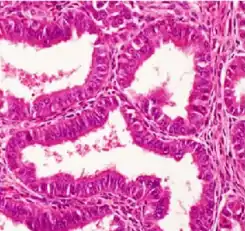

![]() Histopatología de un adenocarcinoma endometrioide bien diferenciado en el ovario | ||

Microscopía óptica

La microscopía óptica muestra glándulas tubulares, parecidas al endometrio [7]